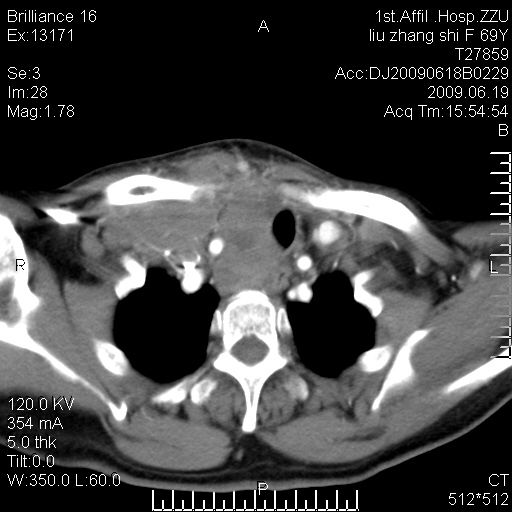

标题: CT26782:女,69岁,颈部占位,3天后公布病理结果。

【病理证实系列】女,69岁,颈部占位,有病理结果,3天后公布。(由于病例时间较久,临床资料不全,请网友见谅)本系列将有几百种常见、少见及罕见病例,均经病理证实。病例资料来自郑州大学第一附属医院。与网友共享,本人有空就发。

甲状腺癌并颈部淋巴结转移。感谢楼主的良苦用心,谢谢。

甲状腺癌并颈部淋巴结转移。

需与鼻咽癌鉴别!

支持甲状腺癌广泛侵及周围结构并颈部淋巴结转移。

鉴别:淋巴瘤、恶性神经源性病变、恶性纤维组织细胞瘤。

病理结果:颈部非霍奇金淋巴瘤。